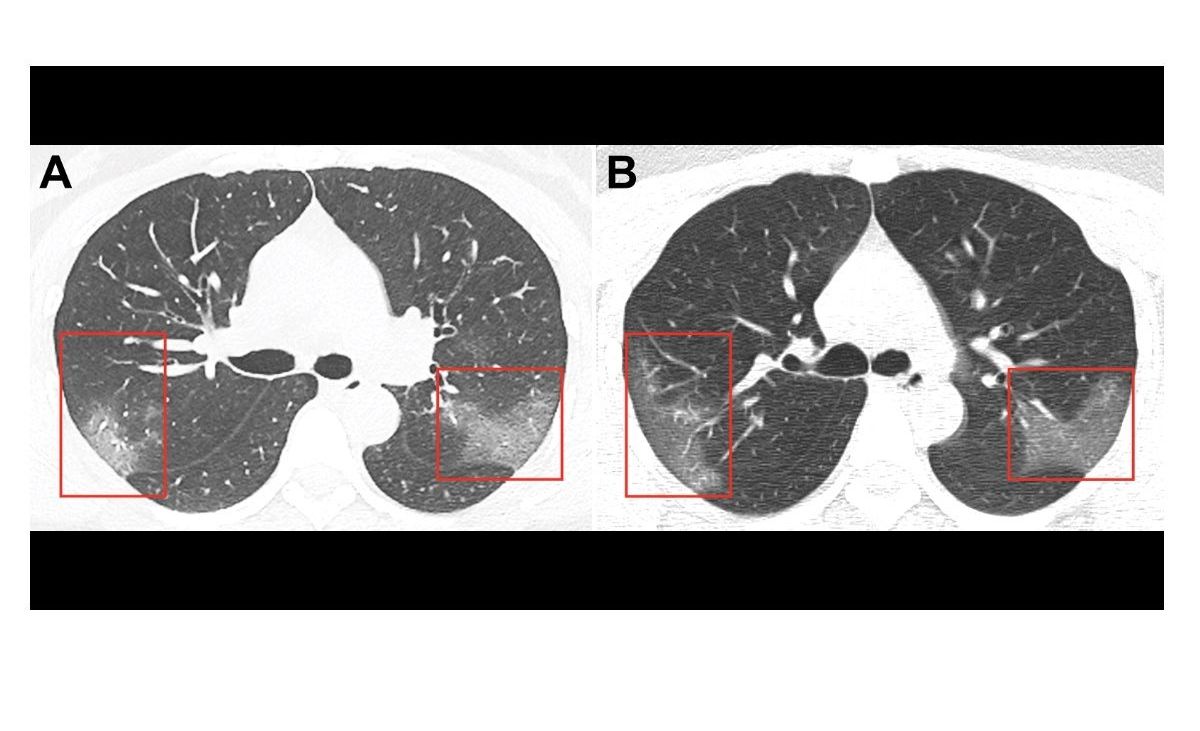

Así lucen los pulmones de una paciente de coronavirus. Crédito: Radiology | Cortesía

Su tomografía computarizada reveló unos parches que se ven como vidrio esmerilado, o líquido en los espacios en los pulmones. Estos son indicios que se encuentran comúnmente en las radiografías de pacientes con casos graves.

Normalmente, a una persona no se le realizaría una exploración del tórax, como en el escenario, pero los médicos hicieron una excepción en su caso. Encontraron opacidad de vidrio esmerilado en sus pulmones, las marcas de la neumonía Covid-19.